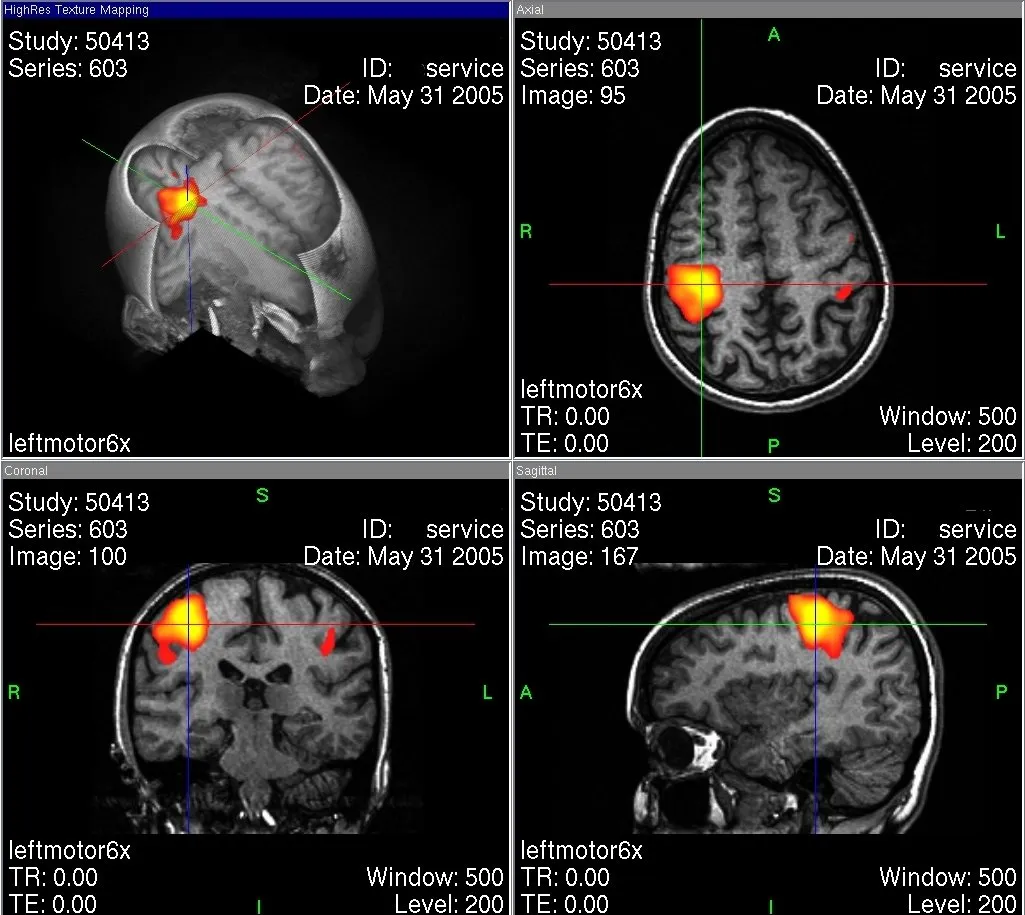

What does that mean to us? Whenever we do a certain activity different regions are used. We might not use all regions at the same time but generally we do use our completely brain and not only ten percent of it. If we would contentiously use all brain regions simultaneously, we definitely would have an overload of information we could not process. In a recent post I explained how we can detect certain regions that are responsible for specific functions. One way to display active brain areas is the functional magnetic resonance imaging (fMRI). It uses the technique of MRI and is able to detect refined distinctions in blood flow. When a brain region is active more blood flows. With help of the fMRI it is possible to see what region is activated when we are happy for instance.

Fig.3 fMRI scans of the human brain. Credits

Recent studies showed that regions that are not used can adapt their functions to those of similar regions. Scientists found out that the regions for sight of blind people just changed and took different functions. The phenomena that our brain can change is called neuroplasticity. Simplified one can say that habits cause our neurons to build paths. Every time we do a certain activity this connection between the neurons becomes stronger. The older we become the stronger these neuronal connections. Relearning things is just because of this fact hard to most of us because our brain uses the most “comfortable” path and building new connections is unfavorable. So when someone tells you, you are too old to change your habits: it’s not true. Is just becomes harder. There is a point I want to add to the fMRI images. It might seem that only the colored region is active. This is only partly true. The brain is always active but the regions that are not in use are in standby, however register signals. They are not marked because their value were set to 0 as a reference.